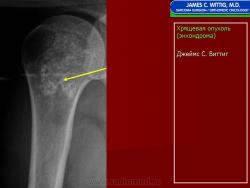

Энхондрома (син.: хондрома, центральная хондрома) — доброкачественная хрящевая опухоль, расположенная в костномозговом канале (интрамедуллярно). Встречается в 10 % случаев от общего числа доброкачественных опухолей костей. Считается, что она возникает из эктопически расположенных островков хряща, отщепившегося от пластинки роста на ранних этапах онтогенеза. В ряде случаев опухоль остается бессимптомной и обнаруживается случайно при рентгенологическом исследовании. В других случаях возникают боль и припухлость. Обычно болезненными становятся все энхондромы фаланг. Наиболее частая локализация: фаланги, главным образом, пальцев кистей, проксимальный конец плечевой кости, проксимальный или дистальный концы бедренной кости. При рентгенологическом исследовании в энхондроме определяются просветления с участками минерализации. Тень кости становится более широкой, кортикальный слой сохраняет целостность, но истончается. В редких случаях энхондрома имеет вид эксцентрически растущего экзофитного новообразования. Макроскопически опухоль представляет собой голубовато-белую полупрозрачную хрящевую ткань, в которую вкраплены желтоватые участки обызвествления. Опухоль состоит из отдельных хрящевых узелков, диаметр которых варьирует в пределах 1 см.

Рентгенологическая картина хондромы представляет четко очерченный опухолевый узел. Очаги минерализации в хондромах выглядят достаточно характерно и представлены очаговыми, глыбчатыми или кольцевидными , арочными отложениями извести. Полного разрушения кортикального слоя трубчатой кости с выходом опухолевых масс в мягкие ткани не наблюдается.